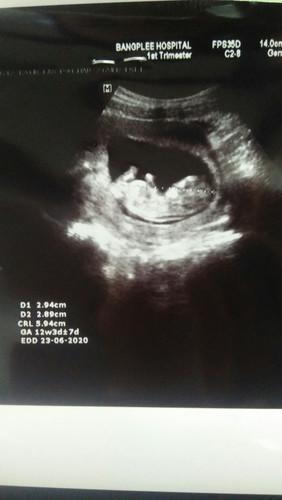

อยากถามแม่ๆว่าคัยดูออกบางคะว่าน้องชายหญิง มีแต่คนทักว่าผู้ชาย

ภาพนี้ไม่บอกเพศค่ะ และที่สำคัญ เพิ่ง 12 วีค ยังไม่เห็นค่ะ อวัยวะยังไม่โตเต็มที่เลย